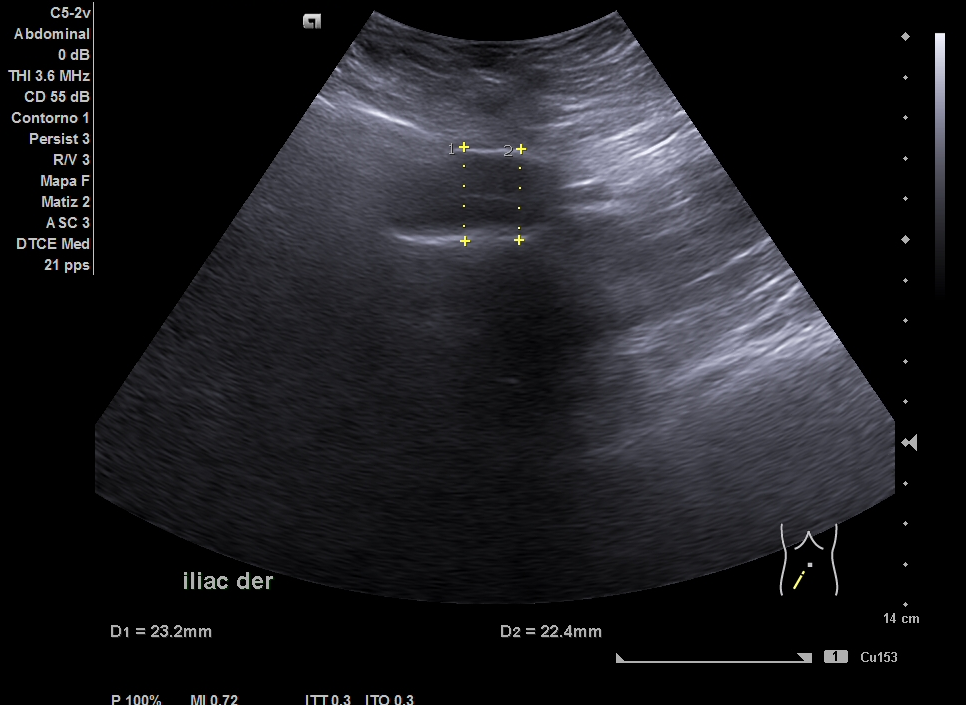

Parenquima hepatico sin alteraciones, vesícula biliar sin imagenes hiperecoénicas en interior. Pancreas visible en parte, sin alteraciones. Asimetría entre ambos riñones compatible variante de la normalidad RI. Llama la atención dilatación ilíaca derecha al comparar con contralateral y con aorta abdominal distal. Compatible con dilatación aneurismática ilíaca derecha.

El diagnóstico diferencial del Aneurisma Ilíaca con: Displasia fibromuscular u otra patología del tejido conectivo, lúes o tuberculosis entre otros. Toda dilatación que sobrepase el 50% del diámetro del vaso se considera aneurismática. Por la edad no se plantea el origen ateromatoso.